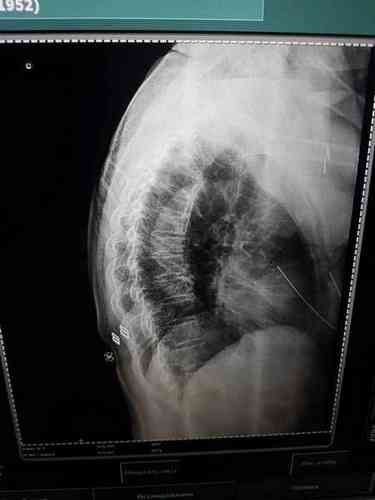

«На мою маму упал чугунный или железный фонарный столб. На голову. В тяжелом состоянии доставили в БСМП, провели обследование, сделали МРТ. Закрытая черепно-мозговая травма, ушиб грудной клетки, компрессионный перелом позвоночника (7 позвонок). Требуется операция на позвоночник», — сообщила девушка.

Позднее Нарбаева добавила, что подтвердился еще и перелом 2-го позвонка.